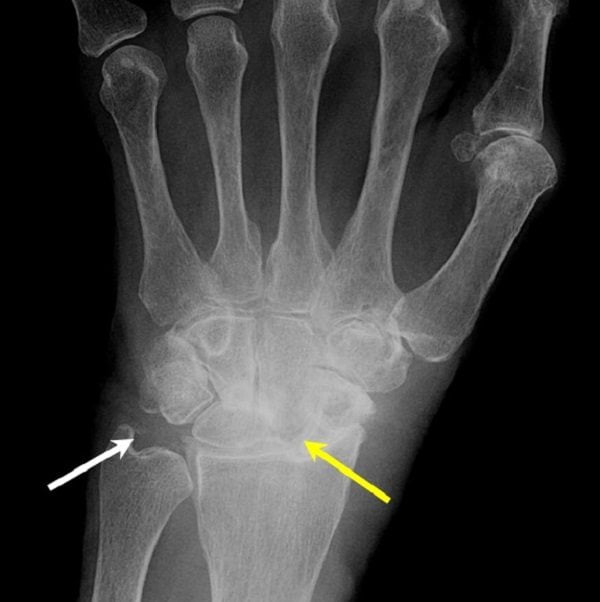

Обнаружить кальциноз суставных хрящей и периартикулярных тканей можно с помощью визуализирующих методов исследования. Наиболее простой — рентгенография. Выраженность клинической картины заболевания обычно не зависит от количества и размера кальцификатов. Часто множественные отложения солей не вызывают никаких симптомов, а типичные признаки артропатии возникают при отсутствии отложений.

Рентгенография позволяет выявить только крупные кальцификаты. А вот небольшие отложения солей можно обнаружить только с помощью УЗИ. Этот метод более чувствительный и специфичный при диагностике артропатий.

| Изменения на рентгенограммах | Появление асимметричных узловатых образований в тканях. На поздних стадиях наступает деструкция хрящей и костей, а кристаллы мочевой кислоты откладываются в костях | Кальцификация хрящей, суставной капсулы, сухожилий и периартикулярных тканей | Отложение солей в околосуставных тканях и местах крепления сухожилий к костям. При рентгенографии позвоночника в его мягких тканях также выявляют кальцификаты |